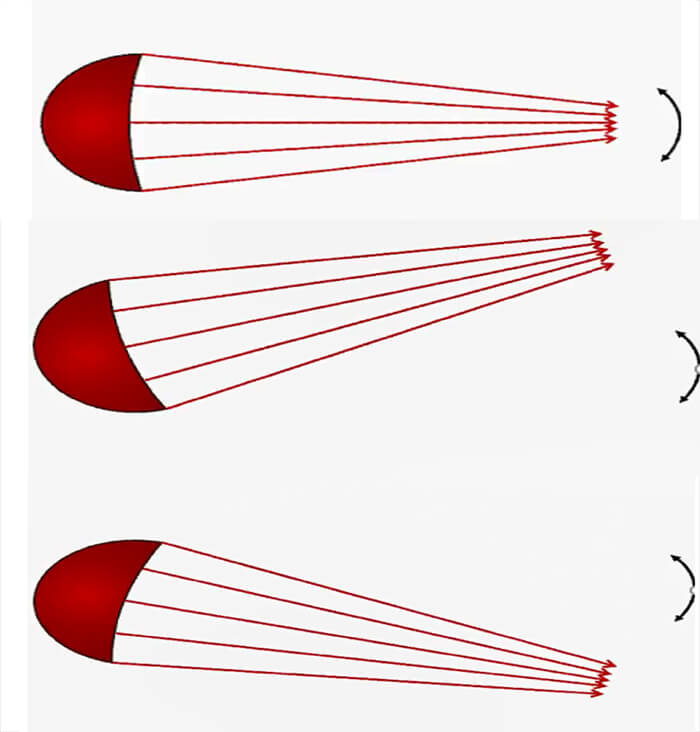

Beam Orientation

Mechanical Scanning

It is important to know that a 2D ultrasound sweeps its field of view using either a mechanical motor or having an array of elements using electronically focused beams that are available in most modern systems. Let’s start with the Mechanical scanning probe, that rotates a single transducer, or array of transducers mechanically. It pulls one pulse in each direction and then waits for the pulse to return before rotating the transducer one step.

Electronic Focusing and Beam-steering

Moving on to the electronic scanning technique, a subset of piezoelectric elements work together to produce the focused beam. Each of the transducers is excited with time offsets. The combination of several focal lengths at the emission improves the quality of the image.

Steering the Beam Electronically through the Scan Plane

The beam is electronically steered to scan a 2D plane.